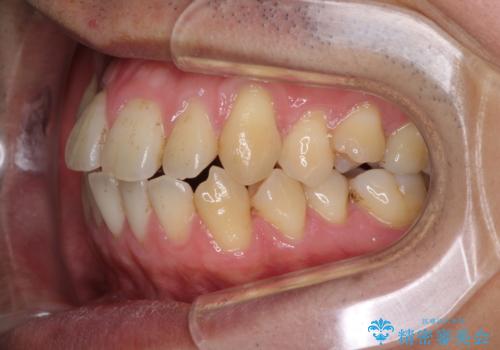

インビザラインによる反対咬合の改善は、上の歯が下の歯を乗り越えていく期間に咬み合わせが非常に不安定となり、治療が長期化することがあります。

また、ワイヤー矯正と異なり歯軸改善の強い力を前歯にかけるため、反対咬合で裏側にある歯の歯肉が退縮しやすくなります。

矯正治療により元々気になっていた八重歯と、反対咬合が改善された歯の2本に対して根面被覆を行い、審美面の改善も達成しました。